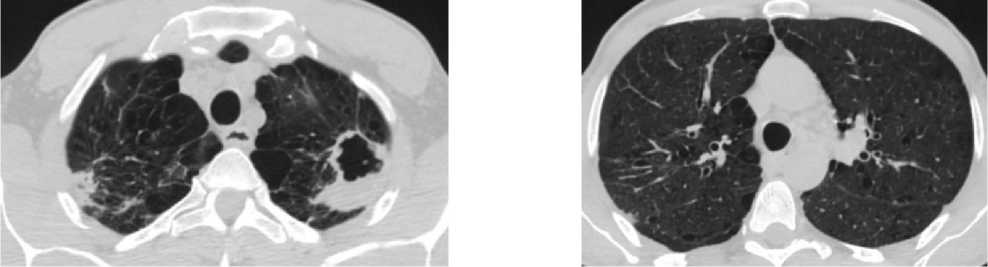

На контрольной КТ ОГК – положительная рентгенологическая динамика в виде частичного рассасывания очагово-инфильтративных изменений в обоих лёгких, определяется зона консолидации неодно- родной жидкостной плотности на месте ранее определявшейся воздушной полости – в большей степени соответствует заполнению полости патологическим содержимым (рис. 2).

а

Рисунок 2. Аксиальные срезы КТ органов грудной клетки, лёгочное окно: а – зона консолидации неоднородной жидкостной плотности на месте ранее определявшейся воздушной полости; б – частичное рассасывание очагово-инфильтративных изменений в обоих лёгких Figure 2. Axial CT scans of the chest organs, pulmonary window: a – a zone of consolidation of heterogeneous liquid density at the site of the previously determined air cavity; б – partial resorption of focal infiltrative changes in both lungs

б